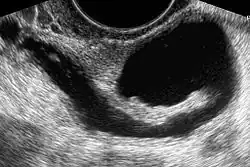

Sonohysterography

Sonohysterography is a specialized procedure by which fluid, usually sterile saline (then called saline infusion sonography or SIS), is instilled into the uterine cavity, and gynecologic sonography performed at the same time. A review in 2015 came to the conclusion that SIS is highly sensitive in the detection of intrauterine abnormalities in subfertile women, comparable to hysteroscopy. SIS is highly sensitive and specific test in the diagnosis of uterine polyps, submucous uterine fibroids, uterine anomalies and intrauterine adhesions (as part of Asherman's syndrome), and can be used as a screening tool for subfertile women prior to IVF treatment.[4]